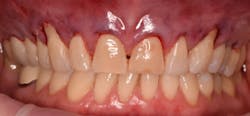

This new biological approach involving blood derivatives A-PRF and I-PRF combined with precision minimally invasive surgery for root coverage demonstrates faster healing without the need of a donor site. The morbidity of GDT is decreased and patient case acceptance is higher compared with traditional grafts. Before-and-after pictures are shown below (figures 15–22).